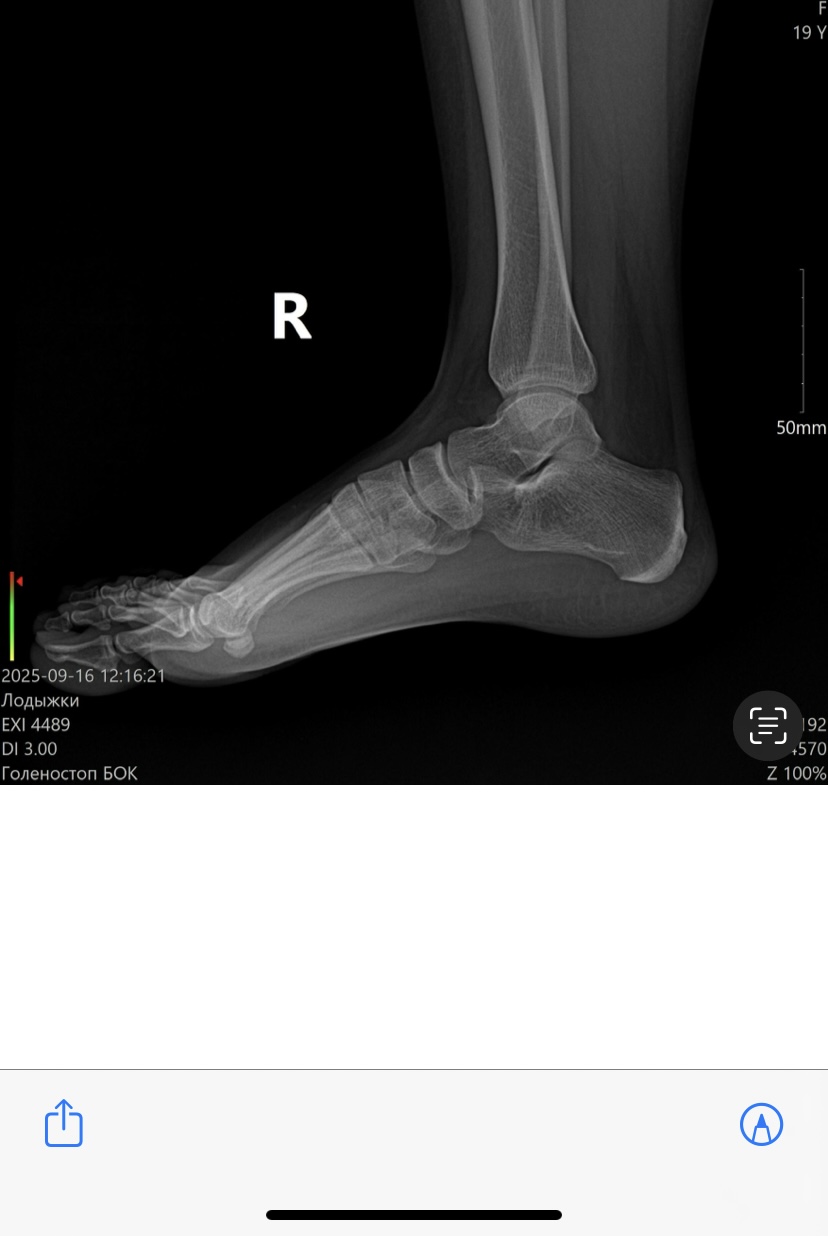

Очень извиняюсь , ни как не получалось  загрузить файлы.  16.09.25 была получена травма : оступилась , подвернула ногу внутрь и упала . В травмпункте диагностировали только растяжение связок и велели наложить бондаж с фиксирующим бинтом. В заключения рентгена кроме кроме разрыва связок , описали кистозное просветление левой ладыжки , как особенность строения?)  это образование почему-то видно только в одной проекции. Что это может быть? Возраст -19лет

Костных травматических изменений не определяется. Округлое просветление в латеральной лодыжке есть.Сверилась с Атласом нормальных вариантов. Это не патология. Просветление обусловлено ямкой в дистальном конце малоберцовой кости.